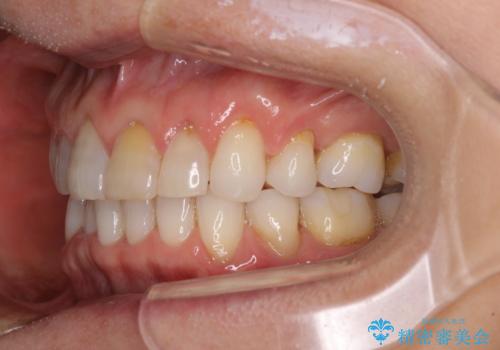

矯正治療の後戻り インビザライン・ライトでの再矯正

- 上下前歯を中心に、以前行った矯正治療の後戻りが気になるとのことで来院された患者様です。

後戻りは軽度であったため、インビザライン・ライトにて治療を行うこととしました。

矯正治療後は、再度後戻りすることを極力回避するために、下顎前歯の舌側を細いワイヤーを用いて保定することとしました。